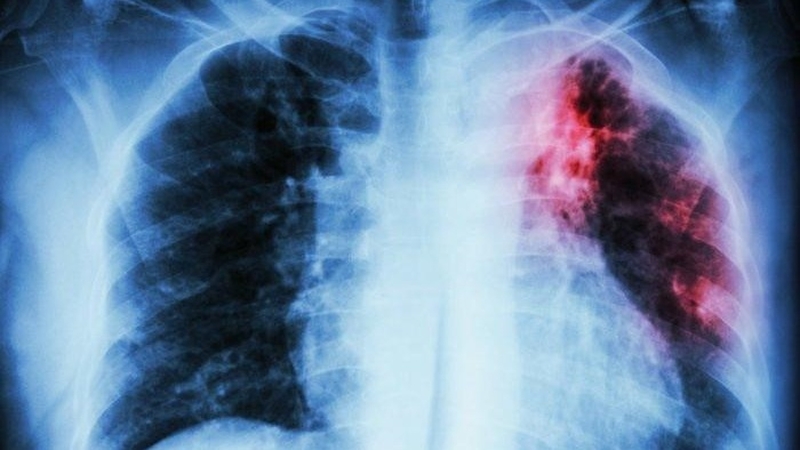

Là tình trạng tổn thương các cấu trúc trong phổi, chủ yếu là phế nang, thường do tác nhân virus, vi khuẩn, nấm hoặc hóa chất độc hại gây ra. Triệu chứng thường gặp là ho nhiều, có đờm và đôi khi có máu trong đờm.

Lao phổi:

Là bệnh lý gây ra triệu chứng ho ra máu. Bệnh nhân cũng có thể có các triệu chứng khác như giảm cân đột ngột không rõ nguyên nhân, đổ mồ hôi vào ban đêm, mệt mỏi và sốt về chiều.

Ung thư phổi:

Nếu khạc ra đờm có máu, người bệnh cần lưu ý về nguy cơ mắc ung thư phổi. Ngoài ra, các triệu chứng khác như thở khò khè, đau ngực, cảm giác chán ăn và mệt mỏi cũng cần được chú ý.